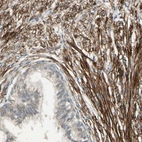

Immunohistochemistry analysis in human placenta and liver tissues using HPA008848 antibody. Corresponding MCAM RNA-seq data are presented for the same tissues.